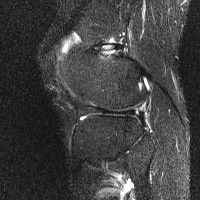

무릎 mri 간단히 봐주실 수 있으시나요 ㅠㅠ

안녕하세요 8년전 십자인대 수술하고 최근 무리한 운동에 무릎 불편감이 생겨서

mri 찍었습니다.

진단결과는 첫 찍은 병원에서 활액막염 이라는 진단을 받았습니다. 혹시 봐주실 수 있으실까요?

올라온 MRI가 단편적이라서 정확한 진단에 어려움이 있지만 십자인대에는 큰 이상이 있지는 않은것 같으며, 무릎관절내 물이 있는 것으로 보아 활액막염의 진단이 맞을 것 같습니다.

하지만 단편적인 영상이기 때문에 촬영병원에서 정확한 판독지 등을 받으시는 것이 좋겠습니다.